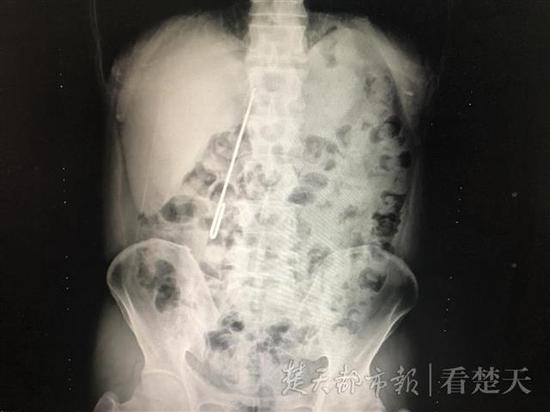

該院肝膽胰外科接診的呂波醫(yī)生為其進(jìn)行了細(xì)致檢查,CT結(jié)果顯示長(zhǎng)針在常先生體內(nèi)十二指腸降部與水平部拐彎交界處,且已穿透十二指腸,尖銳一端在十二指腸外露著,針尖有進(jìn)一步損傷大血管及結(jié)腸風(fēng)險(xiǎn)。因之前胃鏡取出失敗,為避免引起更嚴(yán)重后果,該科副主任醫(yī)師朱新鋒了解患者情況后,決定為其急診手術(shù)。術(shù)中,醫(yī)生將患者胃切開,自胃幽門從十二指內(nèi)取出長(zhǎng)針,探查發(fā)現(xiàn)未傷及大血管及結(jié)腸,十二指腸破口約0.6厘米,又為患者進(jìn)行了十二指腸穿孔修補(bǔ),并進(jìn)行減壓、置入鼻空腸管、充分引流。取出的針的長(zhǎng)度達(dá)16厘米,直徑也有5毫米,術(shù)后經(jīng)積極治療,患者未出現(xiàn)十二指腸漏,已正常進(jìn)食,目前正在康復(fù)中。